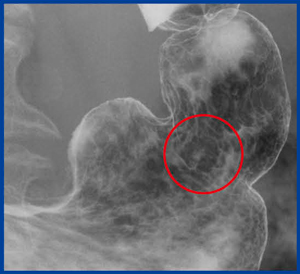

図3は,残胃症例における微小胃がんの内視鏡像である。色調の違いと,小さな顆粒で発見された。

X線画像(図4)では,小さな顆粒と周囲の棘状の変化があり,びらんではないことがわかる。しかし,これを見つけるのは容易ではなく,画像精度は向上したものの,診断には熟練を要することが今後の課題である。

本症例はsignet-ring cell carcinoma(4mm×3mm)と診断され,内視鏡治療(ESD)を施行した。

図3 微小胃がん(4mm×3mm)の内視鏡画像 |

図4 微小胃がん(4mm×3mm,未分化型)の |